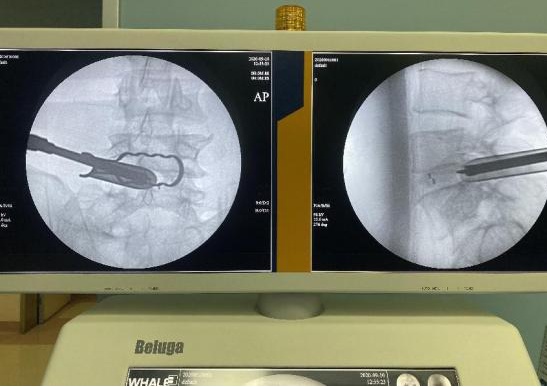

术中透视见椎间融合位置良好